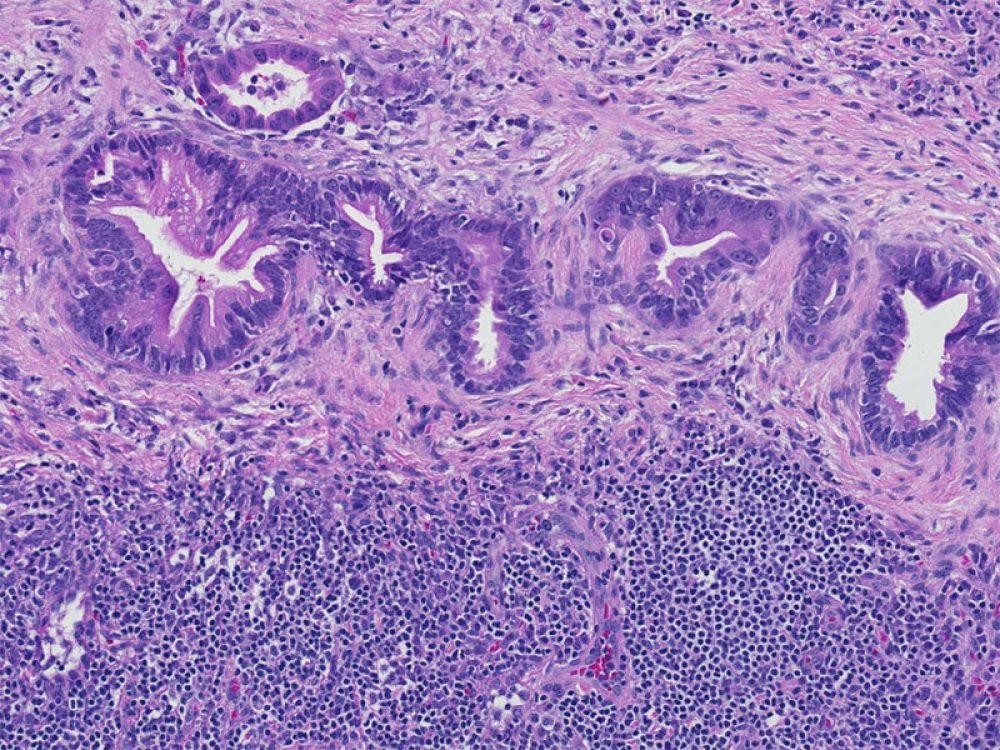

Under the Microscope: Grades of Pancreatic Cancer

The images below are examples of a normal duct and of low-grade and high-grade pancreatic cancer; these slides are what a pathologist sees under the microscope when evaluating the grade of a pancreatic cancer.

Low-grade Adenocarcinoma

Well Differentiated adenocarcinoma

Well-differentiated adenocarcinomas form ducts ("tubes") that, like normal ducts, are lined by relatively uniform cells.